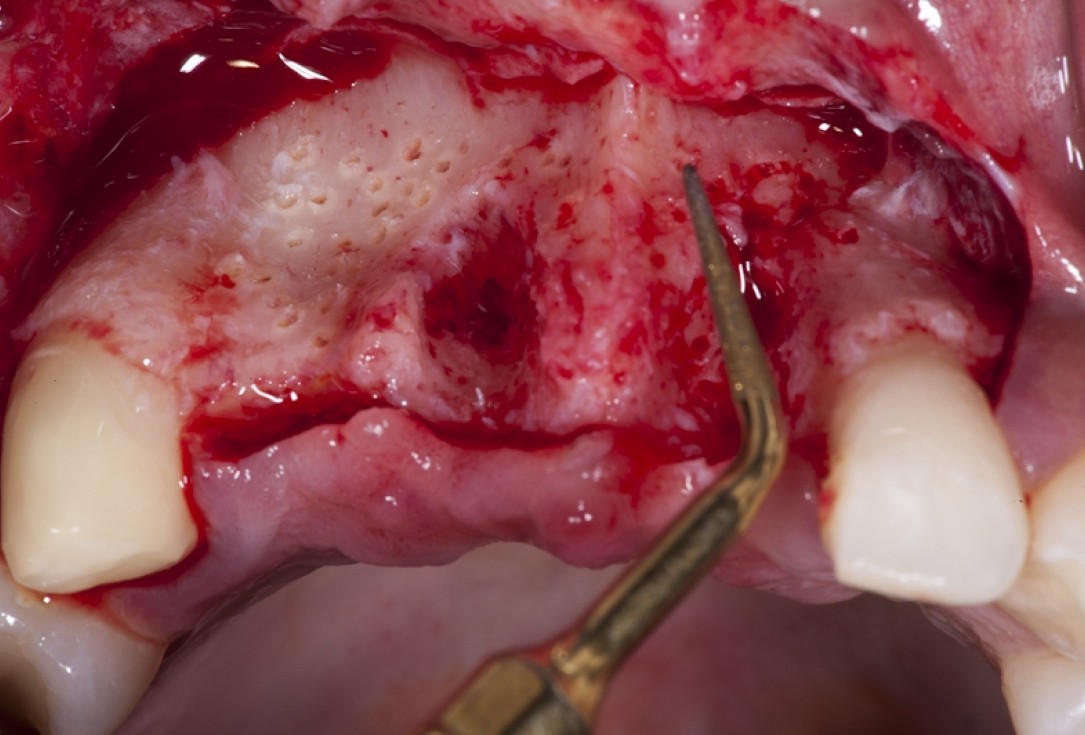

04/17 - Full flap elevation and severe hard tissue exposure